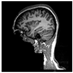

Brain segmentation, also recognized as brain extraction or skull stripping, is a pipeline of segmenting (generally) a T1W brain MRI volume into brain and non-brain regions [8], as portrayed in Figure 1. This is an initial and important preprocessing step of most brain MRI studies, such as brain tissue segmentation and volumetric measurement [9,10], longitudinal analysis [11], multiple sclerosis analysis [12], and cortical and sub-cortical analysis [13]; assessing schizophrenia [14]; and for planning of neurosurgical interventions [15]. Accurate skull stripping is a critical step for a neuroimaging diagnostic system because neither the inclusion of non-brain tissues (skull, dura mater, etc.) nor removal of brain parts (under segmentation) can be rectified in subsequent steps, which can lead to the propagation of error through succeeding analysis. For instance, skull stripping is the first stage in cortical reconstruction and brain volume measurement [16]. The inclusion of non-brain tissue in brain region can leads to incorrect reconstruction of cortical surface and brain volume computation in the later stages. Fein et al. [17] demonstrated that the complete initial skull stripping from brain MRI results in a more accurate and sensitive analysis of voxel-based morphometry (VBM) in brain morphology. Acosta-Cabronero et al. [18] has also investigated the impact of skull stripping on grey-matter segmentation for VBM and proved that this preprocessing step has a major impact on the VBM results. After the detailed structural and functional investigation, Fischmeister et al. [19] revealed that skull stripping is the most important factor to improving the congruence between the Montreal Neurological Institute (MNI) template and normalized brains.

Figure 1.

Skull stripping in brain MRIs. (a) Input 2D brain image in three orientations (coronal, axial, and sagittal), and (b) respective skull stripping in each image. (c,d) Similarly, the skull stripping in brain MRI volume (data from NFBS dataset [24]).